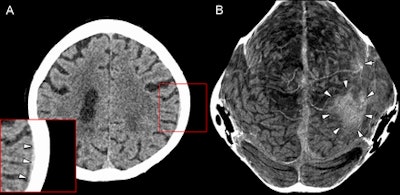

As a result, the Austrian team developed a curved MIP algorithm that unfolds the 3D structure of the meningeal spaces on CT data into four images that are optimized for the detection of meningeal hematomas. For both the skull vault and the skull base, "two curved MIPs were reconstructed: a 3-mm-thick, curved MIP that provides sharp visualization of the epidural and subdural spaces and a 20-mm-thick, curved MIP that covers most of the subarachnoid space as well as the cortex of the brain."

These images are similar to a map of the Earth's sphere that is projected onto a planar image, according to the authors.

"The algorithm is designed to show even very thin or small hematomas at a glance to ease and accelerate the detection process by using thin-section curved [MIPs] of the meningeal spaces," they wrote.